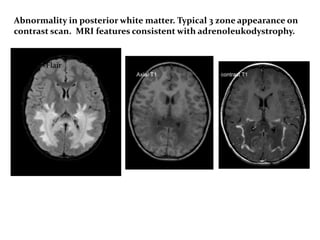

• 7 year old boy with deterioration in school

performance , vision deterioration , reduced

hearing.

• ? Leukodystrophy.

• MRI brain is the investigation of choice.

Flair

Abnormality in posterior white matter. Typical 3 zone appearance on

contrast scan. MRI features consistent with adrenoleukodystrophy.